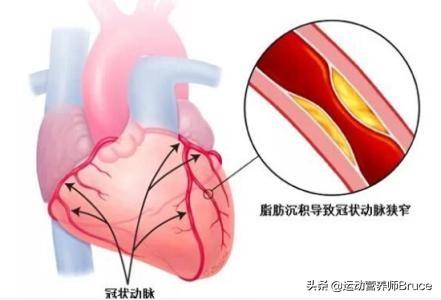

M. Zhu, 47 ans, s'est inquiété lorsqu'un cardiogramme a révélé une sténose de 70 % il y a un an.

Sous les conseils du médecin, en suivant le traitement pendant un an et en menant une vie saine, une récente imagerie de contrôle a montré que la sténose de ce vaisseau sanguin s'était améliorée et n'était plus que de 50 %.

La plaque la plus grave est la plaque cardiovasculaire, ou plaque carotidienne, dont l'aggravation entraîne une ischémie myocardique, une ischémie cérébrale ; si elle n'est pas activement contrôlée, la plaque peut même se rompre et se thromboser, entraînant un infarctus du myocarde ou un infarctus cérébral.

La plaque carotidienne peut être temporairement observée sans médicament si elle est inférieure à 50 % et si le LDL n'est pas élevé ; si la sténose de l'artère carotide est supérieure à 50 % ou si la plaque est molle, il est nécessaire de prendre des statines pour contrôler la plaque. La plaque cardiovasculaire doit également être traitée par statine pour éviter son aggravation. Il est également nécessaire de contrôler activement le diabète, l'hypertension et l'hyperlipidémie, et le LDL devrait idéalement être inférieur à 2,6, voire réduit à moins de 1,8 pour plus de sécurité.

Ces dernières années, les maladies cardiovasculaires et cérébrovasculaires se sont classées au premier rang de tous les types de maladies, et la population a atteint 270 millions de personnes, un groupe important de personnes, l'incidence de la maladie, de sorte que nous ne pouvons pas prévenir, et l'apparition des maladies cardiovasculaires et cérébrovasculaires est due à la formation de la plaque d'athérome.

Il est important de noter queLes patients atteints de plaques artérielles qui présentent un rétrécissement de 50 % des artères ou une formation de plaques instables, en particulier dans les artères coronaires, de la tête et du cou, doivent recevoir un traitement par statines en association avec de l'aspirine. L'association de la statine pour rétrécir et stabiliser la plaque et de l'aspirine pour prévenir la thrombose au niveau de l'endothélium rompu réduit considérablement le risque d'événements cardiovasculaires, ce qui en fait une combinaison classique et un médicament de base pour le traitement des plaques artérielles et la prévention des événements cardiovasculaires et cérébrovasculaires.